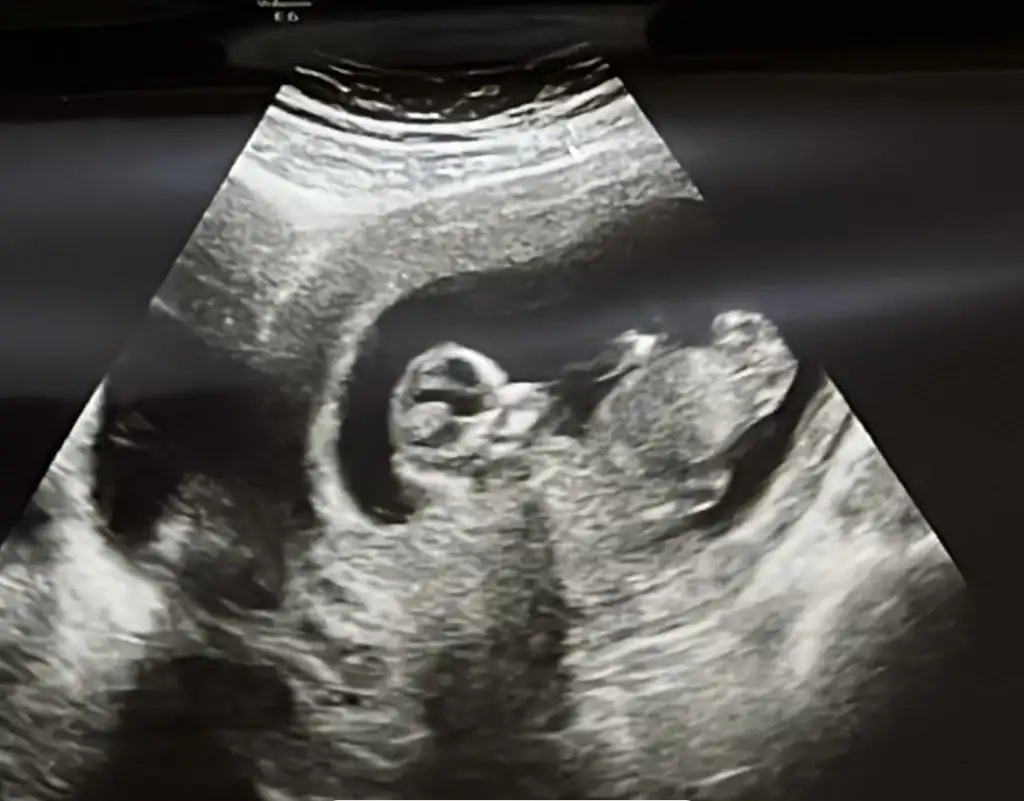

Nub ramzi tahmin edeyim kızlar

Buna göre bakarsam kız derim kuzum :)

Saol kuzum Doktorumda böyle bacak arasını görünce kız gibi ama %70 dedi kesin konusmak istemedi. Bide internetten baktım kız bebekte olan çıkıntı var ultrason fotoğrafımızda. Ama hayırlısı tabi ilk bebeğimiz kız erkek farketmez sağlıklı olsunda

Benim bebek yan durduu hep Dr izledi ve nuba göre kız olduğunu söyledi gerçekten de Bİ nub gözüküyor, net de konuşamam dedi 12ye gidiyordum benn de o sıra.. Bakalım noluyo :) 1 ay snra söylicek :)